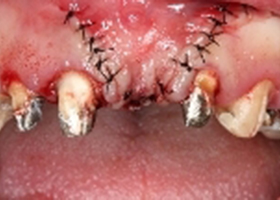

左側側門牙進行牙齦增生手術,解決牙齦萎縮問題。

proimages/case/cosmetic/pic_case-082.jpg

左側正中門牙缺牙,缺牙處植入人工牙根。